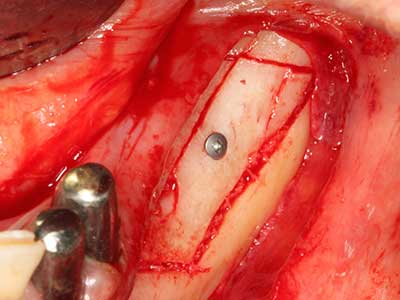

Bone tissue is not simply a mineral structure but also contains a substantial proportion of collagen fibres. This means it not only has good compressive strength but also a degree of flexibility, which can be taken advantage of when performing bone augmentations. In the classical expansion procedure using bone splitting, the atrophied alveolar ridge is split longitudinally and carefully expanded after reaching an adequate osteotomy depth (Fig. 13-16), ideally without substantial removal of the periosteum (Brugnami, Caiazzo et al. 2014, Stricker, Fleiner et al. 2014). Screw and plate systems with increasing expansion distance have proven effective in separating the two bone lamellae while remaining below the fracture threshold. In general, residual bone widths of at least 3–4 mm are required (Chiapasco, Zaniboni et al. 2006) to guarantee adequate flexibility and sufficient bone coverage of the future implants. If necessary, a vertical relief osteotomy on one or both sides can improve flexibility. A combination with additional augmentation techniques, particularly on the buccal side, has been described as an alternative to the classical technique.

The splitting procedure is particularly atraumatic and there is no significant loss of dimension when using piezosaws, and there are no significant differences between implants in split jaws and implants in an alveolar ridge without a bone deficit (Chiapasco, Zaniboni et al. 2006, Danza, Guidi et al. 2009). However, sufficient continuous irrigation is essential, particularly with locally restricted and deep splitting to prevent thermal stress in the apical osteotomy regions.